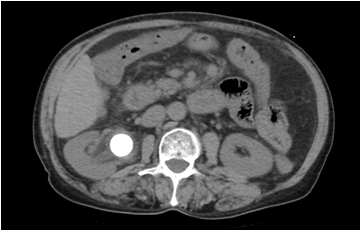

此图为患者泌尿系统ct,可见左侧输尿管中段结石并左侧输尿管中上段,左

图片尺寸2000x2667